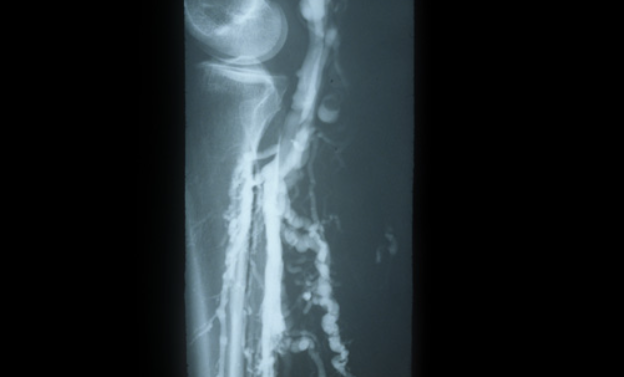

- 정맥초음파 검사와 같은 검진을 통해 정맥 상태를 확인할 수 있습니다.

치료 방법으로는 보존적 치료, 약물 치료, 그리고 수술적 치료가 있으며, 개인의 상태에 따라 적절한 방법을 선택해야 합니다. 전문가와 상담하여 나에게 맞는 치료 방법을 찾아야 합니다.